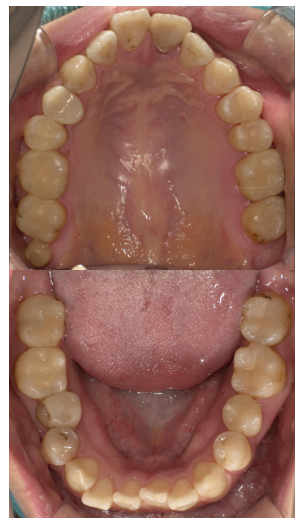

症例2

治療前

治療後

| 主訴 | 虫歯を治したい |

| 診断 |

虫歯 |

| 治療内容 | 保険CAD インレー及びクラウンによる修復 |

| 年齢・性別 |

29歳女性 |

| 治療期間 |

6ヶ月 |

| 治療費用 | 保険に準ずる。目安¥5000×10本 |

| リスク・副作用 | CADの破折、着色 |